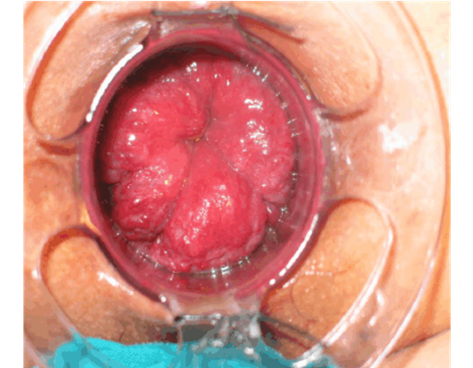

直肠癌可以摸到肿块质地较硬,表面高低不平或呈菜花样,有脓液、坏死组织及暗红色的血液,并感觉肠腔狭窄,指套上也染有暗红色血液。